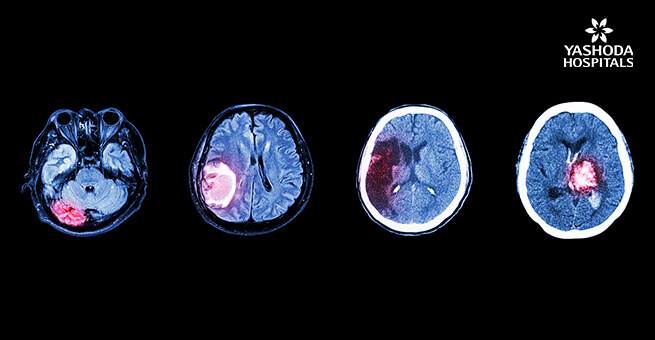

A tumor that can occur at any age , develops in the brain cells . But not all brain tumors are deadly as they can be either noncancerous ( benign) or cancerous (malignant) and can grow slowly or rapidly. They can originate primarily from the brain or can spread as secondary form cancers in other parts of the body. Regardless of the type of brain tumor one has there are treatment options available . It is possible to have a long life even with cancerous brain tumors with the right treatment.

Myth 4: All brain tumors are deadly

Fact :Tumors which are benign are completely curable. Cancerous brain tumors are also curable if they are of low grade. Only the aggressive WHO Grade 4 tumors pose an immediate danger to life and the treatment options are evolving for them.